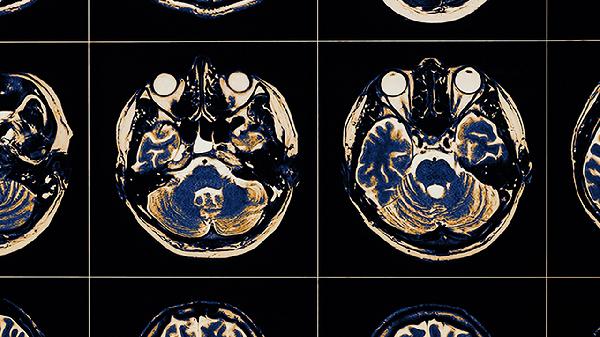

突发单侧上肢或下肢无力是脑血栓的典型前兆,可能与大脑中动脉供血区缺血有关。患者常表现为持物不稳、行走拖沓,严重时可能出现偏瘫。此类症状多由动脉斑块脱落堵塞血管导致,需通过头颅CT或MRI确诊。急性期可遵医嘱使用阿替普酶注射液进行静脉溶栓,恢复期可服用阿司匹林肠溶片预防复发,同时配合血塞通软胶囊改善脑循环。